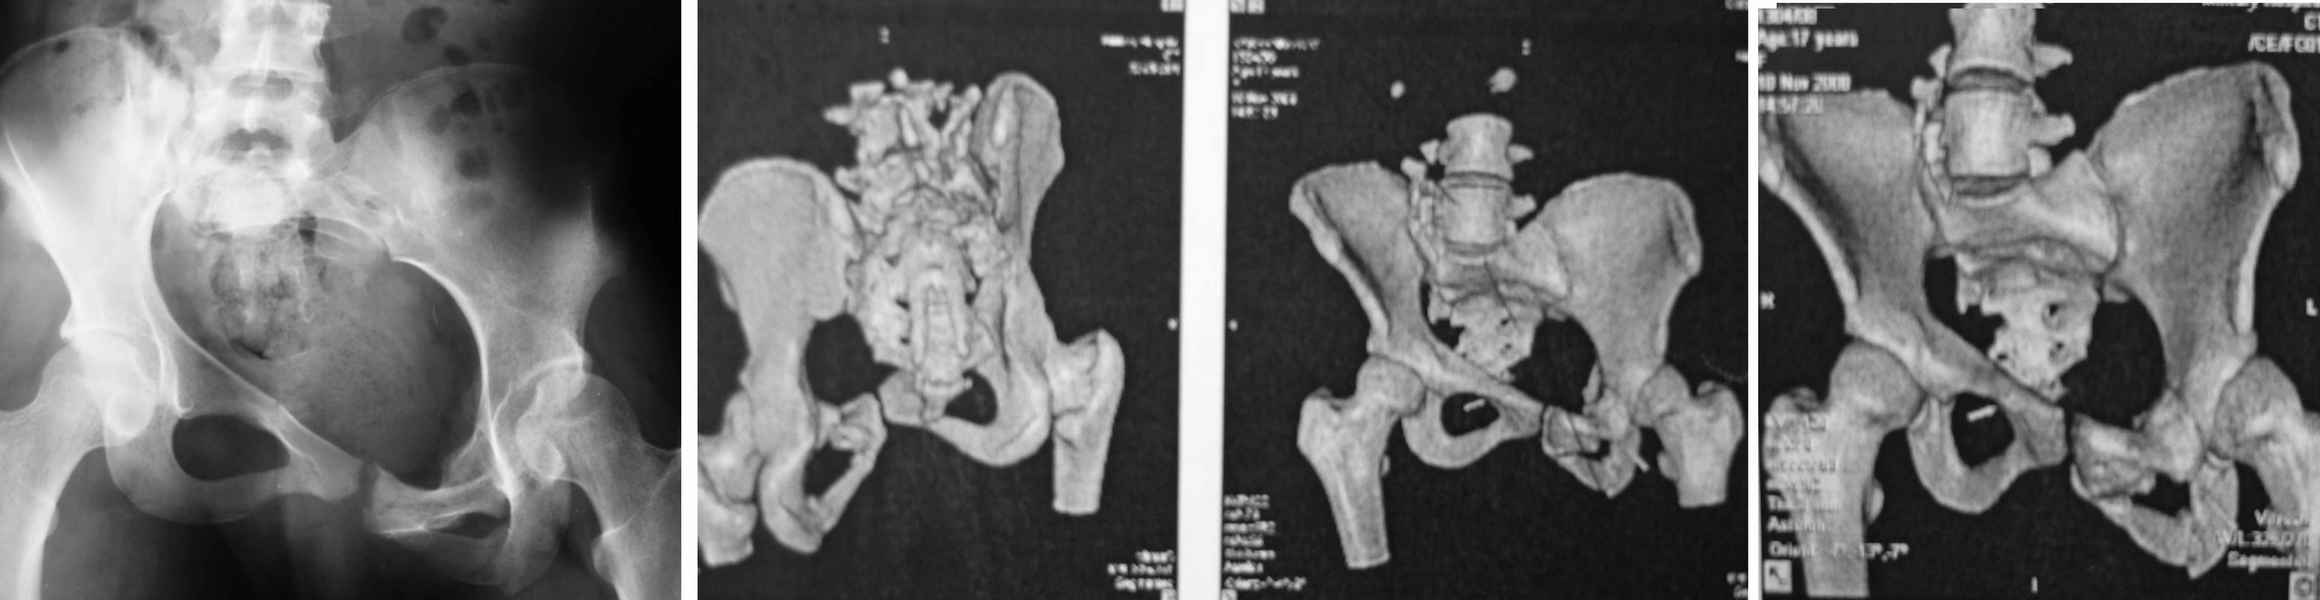

18летняя пациентка 3 месяца назад в результате ДТП получила тяжелую травму таза.

В настоящее время отмечаются неправильно консолидировавшиеся переломы левой лонной и седалищной костей, застарелый разрыв правого крестцово-подвздошного сочленения после закрытого нестабильного повреждения таза (сентябрь 2008 г.) типа 61-С2.

Пациентку беспокоит грубая деформация в области таза, укорочение правой ноги на 3 см. Болевого синдрома, патологической подвижности в области таза нет. Нагрузка на таз безболезненна. Рентгенологические пробы на вертикальную нестабильность отрицательные.